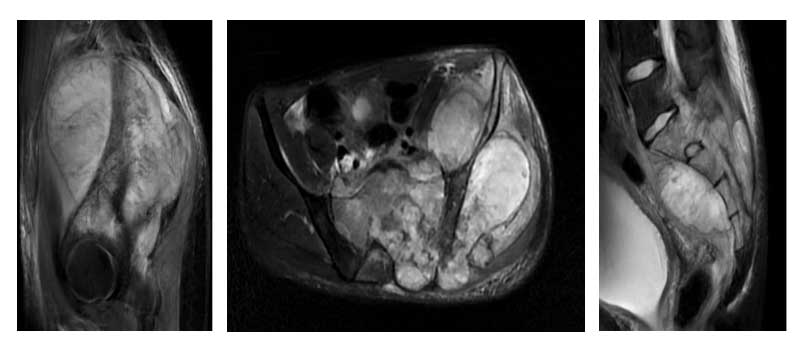

Ameliyat Öncesi: MR’da aynı bölgede büyük yumuşak doku komponentinin eşlik ettiği ve omurilik kanalını dolduran tümör dokusu görülmekte.

24 yaşındaki erkek hastada sakrum ve iliak kanat yerleşimli osteosarkom tanısı sonrası kemoterapi uygulanmıştır. Metastaz saptanmayan hastaya total sakrektomi ve hemipelvektomi sonrası lumbopelvik fiksasyon ve cage ile rekonstrüksiyon işlemi yapılmıştır. Yara kapatılması karın ön duvarından kaslı flep (VRAM) çevrilerek gerçekleştirilmiştir.

• Sakrum ve iliak kanat yerleşimli osteosarkom tanısıyla kemoterapi tedavisi uygulanmıştır.

• Metastaz saptanmamıştır.